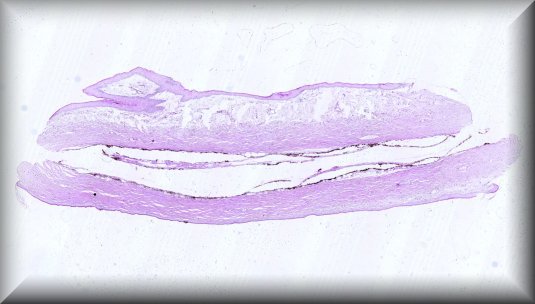

Steffen Heegaard (Copenhagen): Ligneous conjunctivitis in a 12-year-old Turkish girl |

|